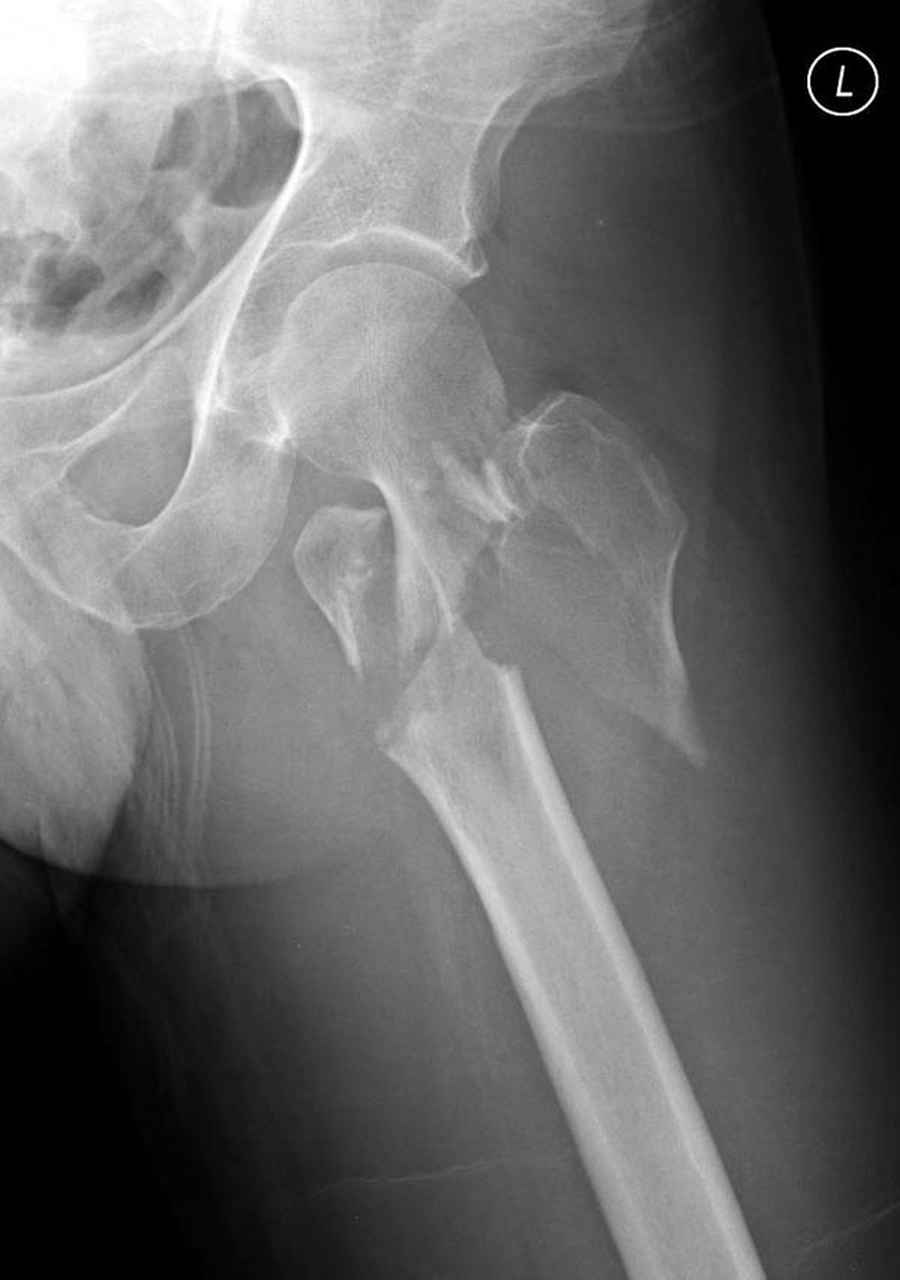

Здесь 83 года, травма в результате падения